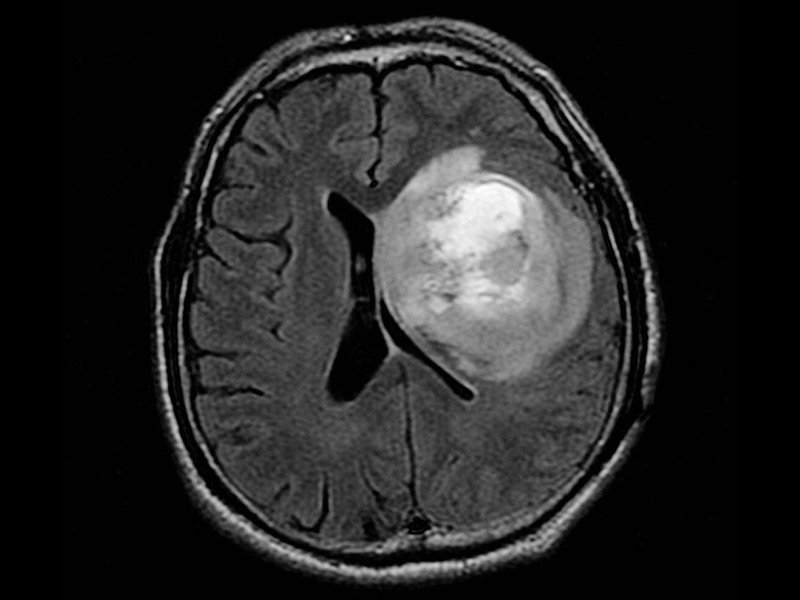

2、侵袭扩散性:胶质瘤不转移扩散说的只是不转移扩散到大脑脊髓外的器官。但是胶质瘤有的可以扩散到整个大脑,在那里它们与正常的健康组织混合。这使得他们很难通过手术切除。很难将肿瘤和健康组织分开。如果外科医生甚至留下一些胶质母细胞瘤细胞,这些残余物可以继续通过大脑传播。在一项研究中,尸检时,45%的多形性胶质母细胞瘤(GBM)延伸至单叶外,25%累及整个大脑半球,25%至30%的病例跨越至对侧半球。近60%的侧位幕上胶质瘤呈前后方向扩散,约20%沿纤维束垂直侵犯幕上深部结构和幕下区,9例额叶胶质瘤经胼胝体(CC)侵犯额叶,颞叶胶质瘤易侵犯中脑和脑桥。在高级别和低级别胶质瘤中都可以观察到这些趋势。起源于CC以下的胶质瘤主要局限于基底结构,如丘脑和沿皮质脊髓束的脚梗。双侧伸展通过丘脑、下丘脑和前连合,是基底节区。事实上,Scherer发现全部丘脑和下丘脑胶质瘤都向两侧延伸。8脑桥肿瘤经常向头部扩散并侵犯中脑和丘脑区域。偶尔,尾侧直接扩散到上颈髓。在未经治疗的病变中,肿瘤细胞在坏死组织的3cm范围内观察到,而在复发时,肿瘤细胞远远超出原发肿瘤,80%的病例在对侧半球发现。

侵袭扩散性带来的另一个关键问题是,无法切除的剩余的肿瘤细胞不可避免地渗透到周围的正常脑组织中,从而导致肿瘤复发。

5、手术作为胶质瘤治疗的一线方案。然而面对脑干、丘脑、胼胝体或基底节等复杂位置时,仍然存在手术难点。但在当前医疗技术水平下,以上“手术禁区”内疑难位置胶质瘤手术全切已经成为现实,当然这需要选择一个在此方面有着较为丰富经验和海量成功病例的手术团队。